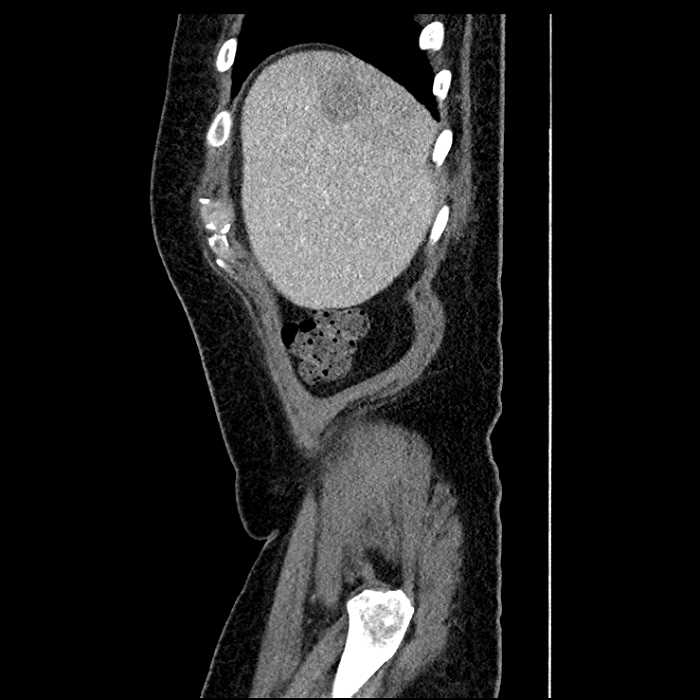

• Large fluid density structure in hepatic segments 7 and 8 measuring 10 x 7 x 7 cm with internal septation and circumferential ill-defined low density compatible with edema

• Clearly marginated fluid density structure in segment 7 and several other scattered tiny hypodensities, which likely represent cysts

Acute sigmoid diverticulitis complicated by a small contained perforation and a large abscess in the right hepatic lobe. Additional small subcapsular abscesses along the anterior margin of the left hepatic lobe.

• The classic CT imaging appearance is a double target sign with internal low density surrounded by an internal enhancing rim (capsule) and a low density external rim (edema)

• Abscesses may be unilocular or multilocular

• Gas is present in a minority of cases

Hepatic abscess showing the double target sign with low density internally surrounded by a thin inner enhancing rim (red arrow) and ill-defined outer low density rim (yellow arrow). Blue arrow indicates an internal septation. Red arrows: additional smaller subcapsular abscesses. Red arrow: focal contained perforation associated with diverticulitis.